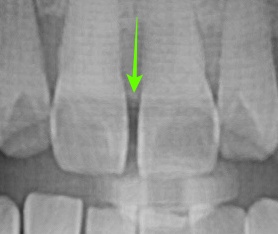

또한, 단지 심미적으로만 치료된 게 아니라 잇몸 건강 측면에서도 매우 치료가 잘 되었습니다.

오른쪽 사진의 노란색 화살표를 보시면 레진과 치아 사이에 턱진 곳이 없으며 부드럽게 이행되는 모습을 볼 수 있습니다.